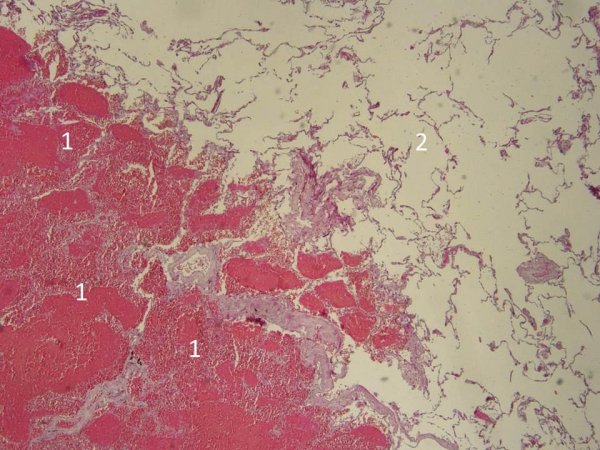

Красный инфаркт легкого микропрепарат

Геморрагический инфаркт легкого микропрепарат